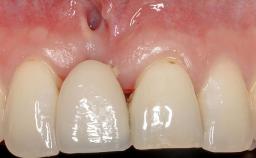

Early Implant Placement, Contour Augmentation, and Autologous Connective-Tissue Graft Using a Tunneling Technique to Replace an Upper Incisor with Generalized Gingival Recession

Variations in soft-tissue volume, evidenced either by an overabundance (Evian and coworkers 1993; Levine and McGuire1997; Dolt and Robbins 1997) or by a deficiency of soft or hard tissue can complicate implant-supported rehabilitations in the esthetic zone (Lorenzana 2008; Lorenzana and coworkers 2009). The present case illustrates the replacement of a failing upper left lateral incisor complicated by generalized severe gingival recession in the esthetic zone.